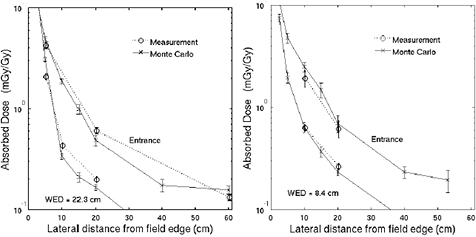

Pediatric patients are traditionally considered a main motivation for proton therapy. About 10% of the patients treated with protons in 2014 were pediatric (Jermann 2015). Dosimetric studies of proton radiotherapy compared with best available photon based treatment show significant dose sparing to developing normal tissues (Armoogum and Thorp 2015). Clinical data are now emerging that begin to quantify the benefit in decreased late treatment effects while maintaining excellent cancer control rates. A prospective study on health-related quality of life at the Massachusetts General Hospital in Boston shows that pediatric brain tumor survivors treated with protons compare favorably to those treated with x-rays and similar to healthy controls (Yock et al 2014). One major concern about late effects in pediatric patients is the induction of second malignant neoplasms. Owing to the reduced exposure of the normal tissues, protons are expected to reduce the risk compared to photons (Xu et al 2008, Newhauser and Durante 2011). Concern has been raised about the possible role of neutrons in the induction of second cancers (Brenner and Hall 2008), a problem relevant for both high-energy x-ray therapy (>8–10 MV, threshold for photoneutron production) and CPT. However, neutron production is drastically reduced using raster scanning, where the beam energy is changed actively rather than using passive modulators. As a result, the distal dose is much lower with protons or C-ions delivered by scanning than with CPT in passive modulation or 25 MV x-rays (La Tessa et al 2012). In line with the predictions of the model calculations, the first epidemiological studies from the Massachusetts General Hospital show that the incidence of second malignancies in patients treated during childhood with protons is lower than for x-rays (Chung et al 2013, Sethi et al 2014).

The nuclear fragmentation processes are essential for the calculation of the beam transport and the prediction of their effects. In proton therapy, only target fragmentation occurs resulting predominantly in secondary protons or neutrons. As shown in figure 12, inelastic scattering enhances the lateral spread of the beam. In addition, the creation of slow, densely ionizing recoil nuclei may enhance the biological effectiveness of the beam. In heavy ion therapy, fragmentation severely reduces the fluence of primary ions: in a typical C-ion therapy treatment, only 50% of the ions actually reach the Bragg peak, the others undergoing fragmentation (figure 14). In addition to the lateral spread, these secondaries contribute to the longitudinal spread of the beam (tail in figure 2). Fragmentation can be exploited as a tool for image-guided CPT (see section 5).